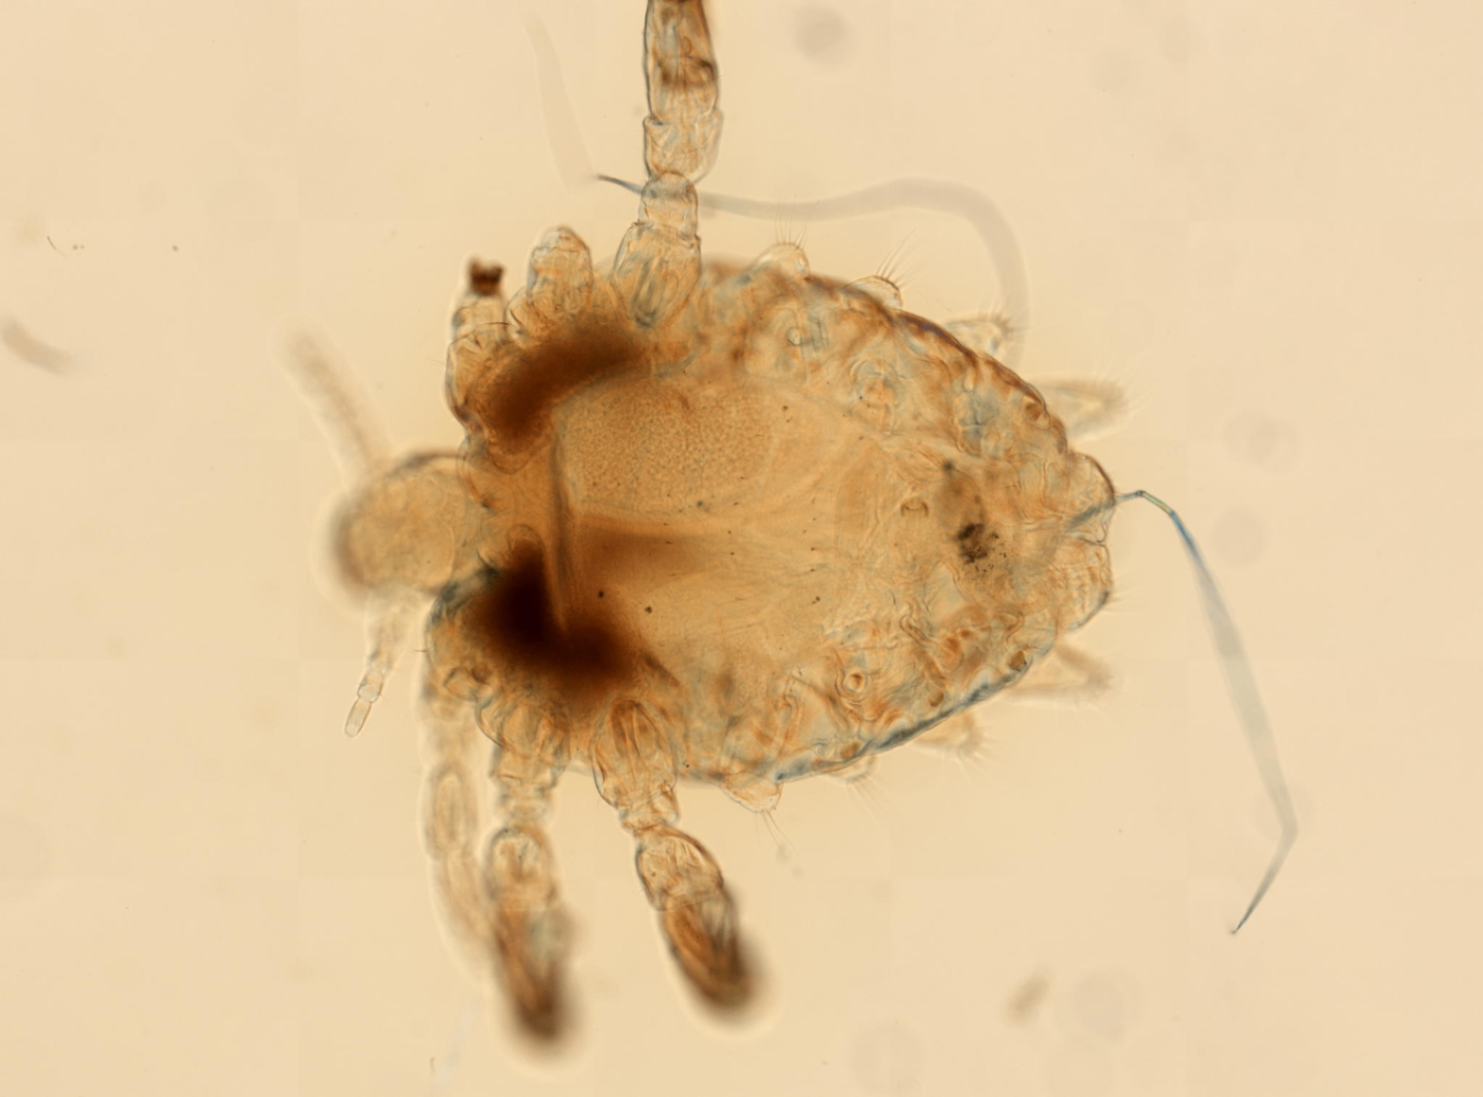

1) 옴진드기

: 사람 피부에 들어와 기생하며 전염성 피부질환인 옴(scabies)을 일으키는 절지동물.

: 감염된 사람과의 직접 피부 접촉 또는 침구류, 의복을 통한 간접 접촉으로 전파

: 겨드랑이, 손가락 사이, 음부 등 간찰부에 많이 생기며 집단 생활을 하는 곳에서 걸리기 쉽다. 극심한 가려움증과 물집을 유발한다.

An Overview of Scabies – MicroBiotics